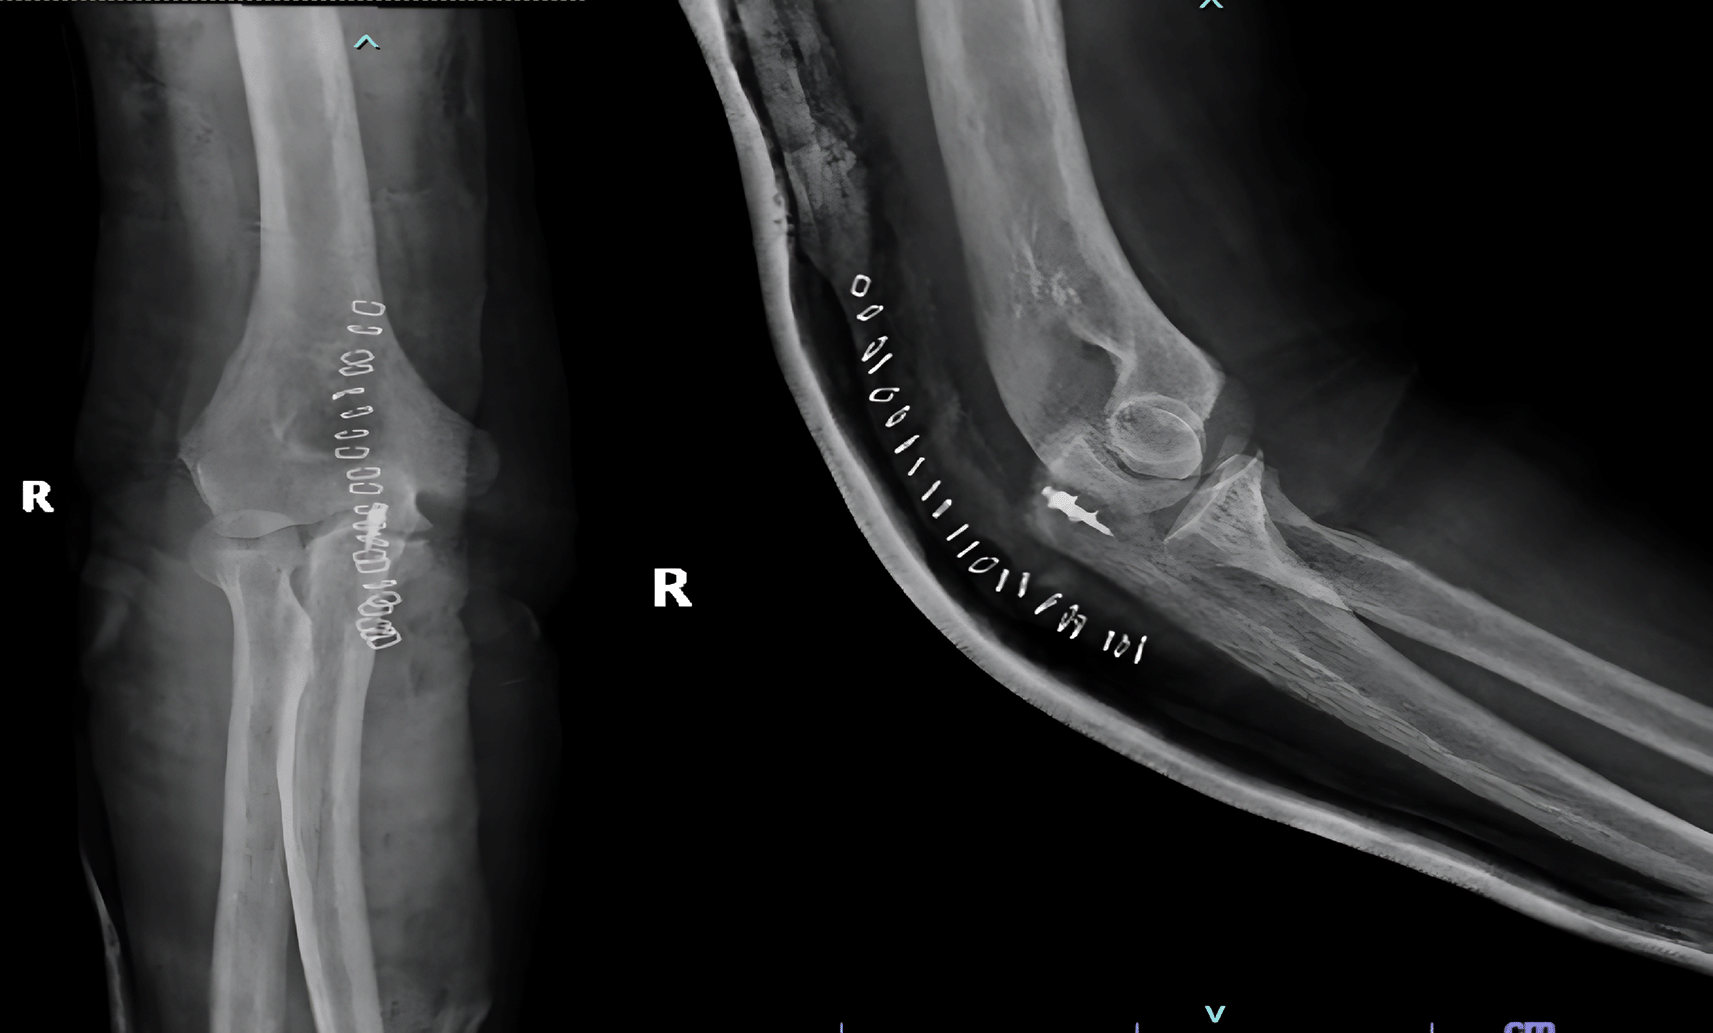

A 44-yr old male with ESRD secondary to immunoglobinA nephropathy with a history of allograft rejection during three weekly hemodialysis sessions for 10 years presented with complaints of right elbow extension weakness following trivial trauma. Physical examination revealed swelling of the right elbow with grade 0 power in the elbow extensor mechanism. Radiographs showed an avulsed triceps tendon (Figure 3).

Figure 3. Anteroposterior and lateral radiographs of Case 2 with avulsed triceps tendon.

He underwent open repair of the triceps tendon with a suture anchor inserted in the olecranon after excision of the devitalized tongue of the tissue (Figure 4). The elbow was immobilized in an above elbow slab at approximately 110° for 6 weeks, after which active mobilization was started. The last follow-up at 7 months revealed grade 5/5 power with full elbow ROM.

Figure 4. Post-operative radiographs after fixation of tensons using suture anchors.